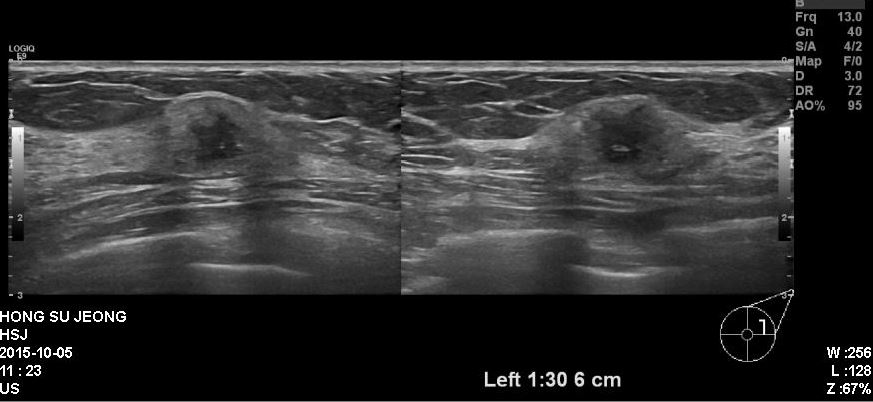

정기유방초음파 시행위해 내원하신  40대환자분이십니다.

본원에서 시행한 초음파상 우측유방 1시30분 방향에 이전과 다른 양상보이는 혹발견되어

조직검사 시행하였고 결과상 침윤성 유관암 진단되었습니다.